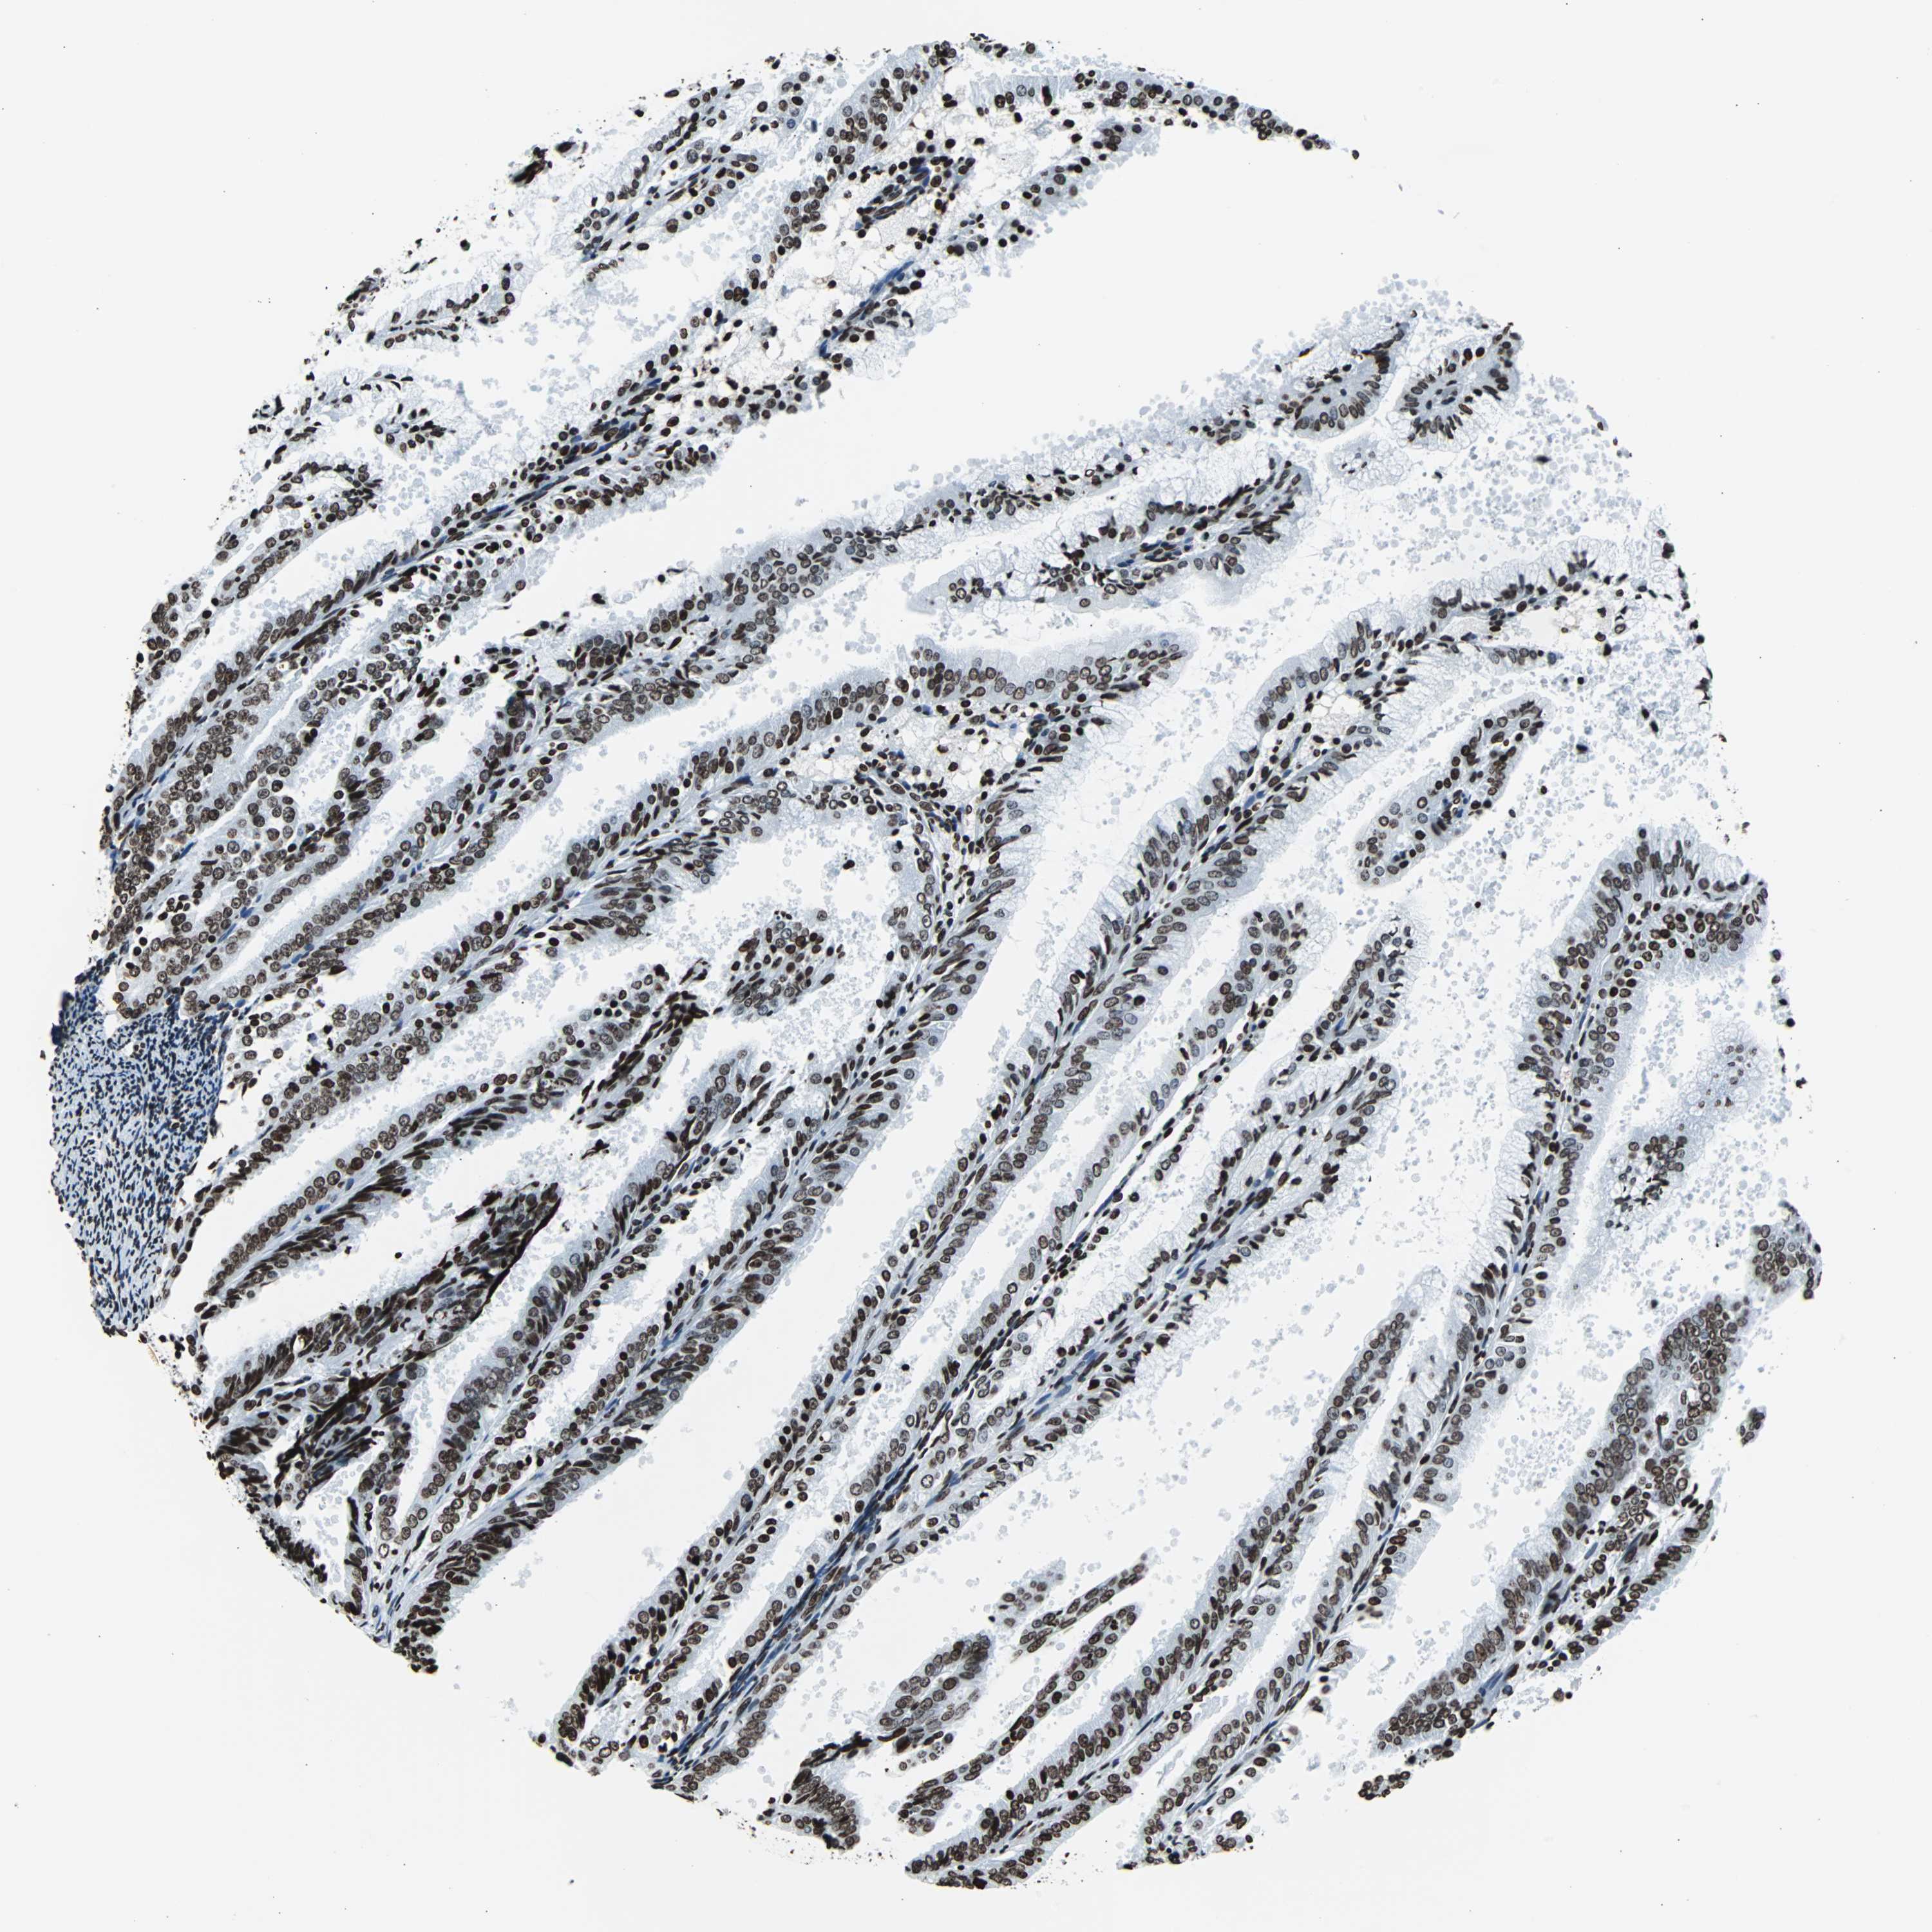

ENDOMETRIAL CANCER - Protein expressioni

A mouse-over function shows sample information and annotation data. Click on an image to view it in a full screen mode. Samples can be filtered based on level of antibody staining by selecting one or several of the following categories: high, medium, low and not detected. The assay and annotation is described here.

Note that samples used for immunohistochemistry by the Human Protein Atlas do not correspond to samples in the TCGA dataset.

Antibody stainingi

Antibody staining in the annotated cell types in the current human tissue is reported as not detected, low, medium, or high, based on conventional immunohistochemistry profiling in selected tissues. This score is based on the combination of the staining intensity and fraction of stained cells.

Each image is clickable and will lead to virtual microscopy that enables deeper exploration of all samples and also displays staining intensity scores, fraction scores and subcellular localization as well as patient and tissue information for each sample.

Antibody HPA042205

Antibody HPA043013

Antibody HPA048671

Antibody CAB007814

Staining

High

Medium

Low

Not detected

Intensity

Strong

Moderate

Weak

Negative

Quantity

>75%

75%-25%

<25%

None

Location

Nuclear

Cytoplasmic/membranous

Cytoplasmic/membranous,nuclear

Adenocarcinoma, NOS